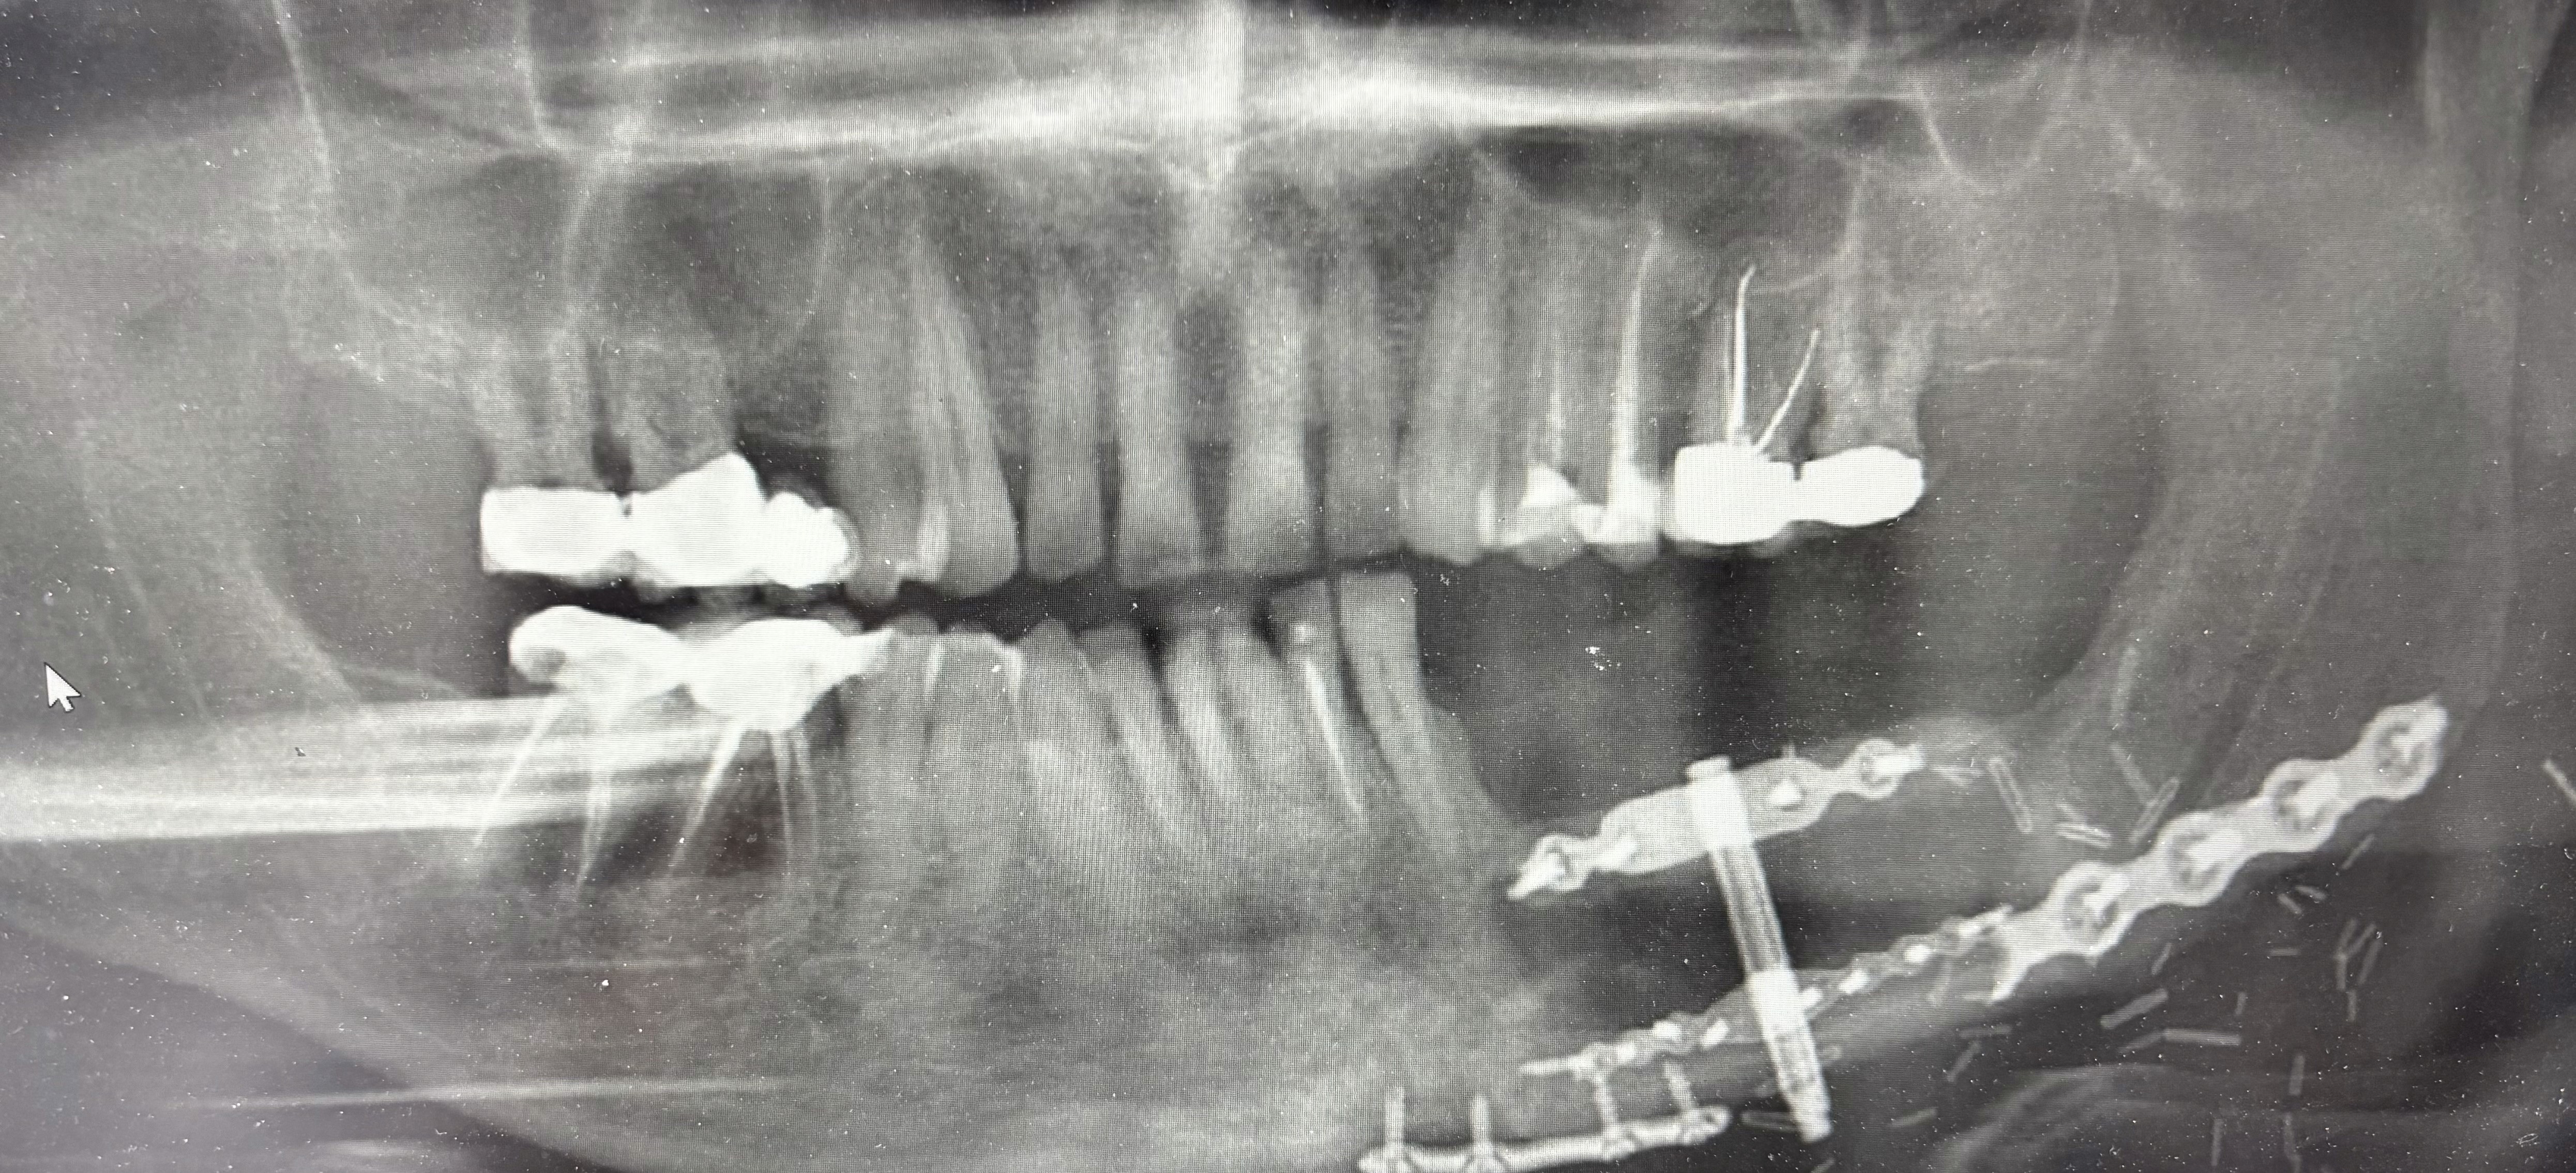

Insertion of distractor for placement of implants on a fibula flap post mandibula excision